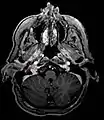

Gallium-68 DOTATATE PET/CT imaging modality may be used to confirm the presence of a paraganglioma.[13]